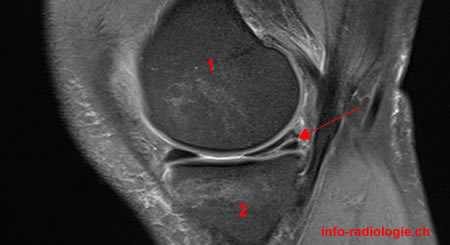

Un patient s’est présenté aux urgence pour blocage aigu du genou, une IRM est réalisée que voit-on?

Anse de seau luxée dans l’échancrure intercondylienne